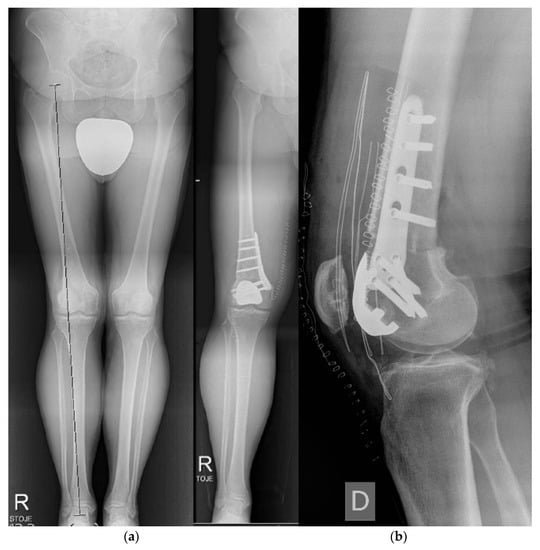

- Brumat, P.; Mihalič, R.; Kovač, S.; Trebše, R. Acute Femoral Lengthening in Adults Using Step-Cut Osteotomy, Traction Table, and Proximal Femoral Locking Plate Fixation: Surgical Technique and Report of Three Cases. Indian J. Orthop. 2022, 56, 559–565. [Google Scholar] [CrossRef]

- Brumat, P.; Mihalič, R.; Benulič, Č.; Kristan, A.; Trebše, R. Patient-Specific Template and Electromagnetic Navigation Assisted Bilateral Periacetabular Osteotomy for Staged Correction of Bilateral Injury-Induced Hip Dysplasia: A Case Report. J. Hip Preserv. Surg. 2021, 8, 192–196. [Google Scholar] [CrossRef] [PubMed]